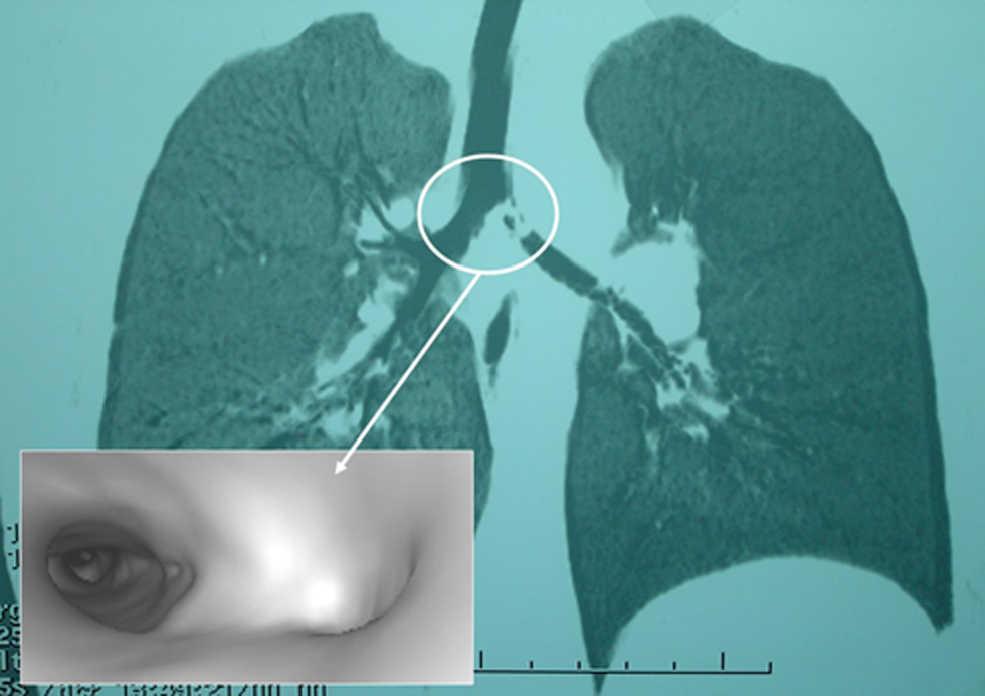

En el momento de la consulta, el niño presentaba una tos seca y continua, pero estaba afebril y sin dificultad respiratoria asociada, con saturación de oxígeno del 97% (fracción inspiratoria de oxígeno de 0,21). No se evidenciaban asimetrías torácicas. En la auscultación había disminución de murmullo vesicular en hemitórax izquierdo. Se realizaron radiografías de tórax anteroposterior y de decúbito lateral que demostraron asimetría de vascularización de ambos hemitórax —menor en el lado izquierdo— así como dudoso atrapamiento aéreo de ese mismo lado en el decúbito lateral izquierdo, que se interpretó como dentro de la normalidad. Pero en la TC-RPM torácica realizada posteriormente se observó un defecto de repleción en bronquio principal izquierdo que ocupaba la práctica totalidad de la luz; la BV no permitía ver la luz del bronquio principal izquierdo (fig. 1).

Figura 1. La tomografía computarizada con reconstrucción multiplanar muestra un defecto de repleción en el bronquio principal izquierdo y un detalle de la broncoscopia virtual que confirma la ausencia de su luz.